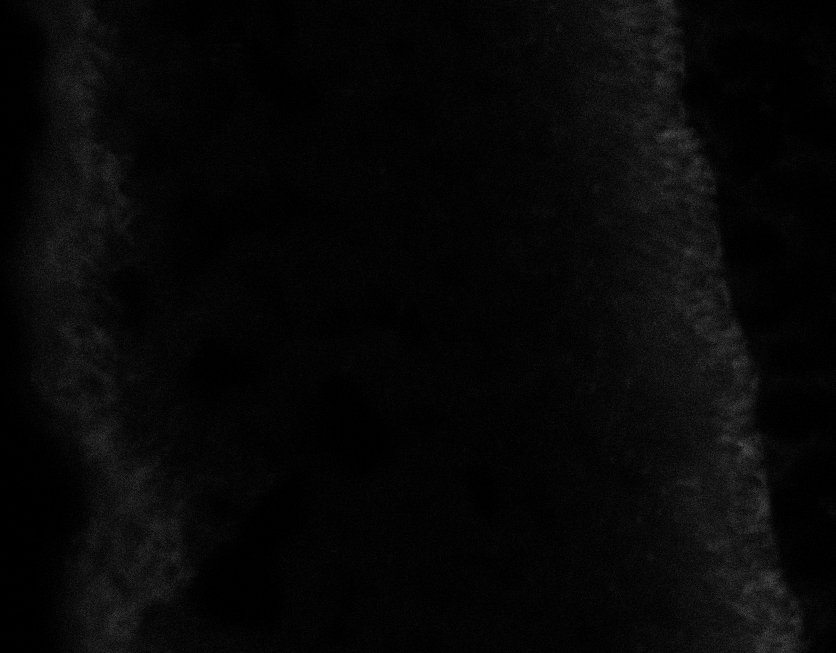

Healthy Retina

Unhealthy Retina

Healthy Eye

Blast Eye